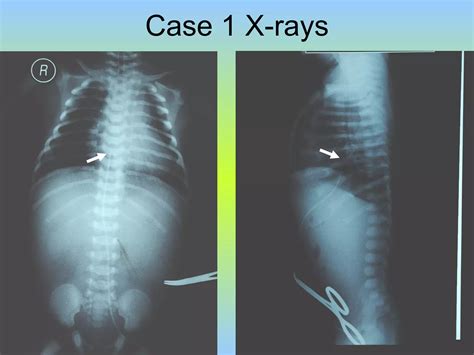

3. Insertion: The catheter is gently inserted into the umbilical vein, which is identified by its larger size and bluish color compared to the arteries. The catheter is advanced until it reaches the desired position, typically confirmed by ultrasound or X-ray.

5. Verification: The position of the catheter is verified using imaging techniques to ensure it is correctly placed in the inferior vena cava.

• Malposition: Incorrect placement of the catheter can lead to ineffective therapy or complications such as arrhythmias.